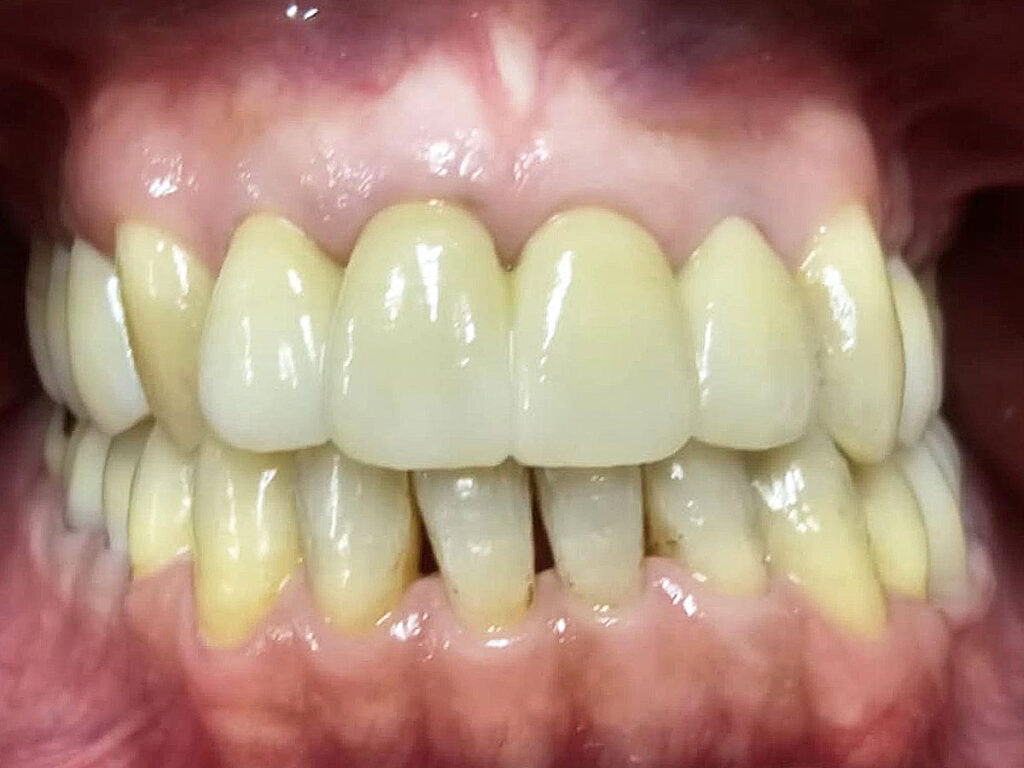

術後

治療期間は約3年でした。本来、外科矯正も視野にいれた方が良いかもしれない、ウルトラE難度のケースだったと思います。しかし年齢的な問題、歯の問題も解決しないといけないため、歯並びは治っても骨格的な問題は解決できないと患者さんに最初に説明してから治療に入りました。しかし、本人最終的な仕上がりには大変満足しているようです。

更に化膿していた歯根も全て当医院の再治療で完治したことがCT画像でもわかるため、大変感謝されました。ただ、本来アレルギー体質も考慮して、全てメタルフリーという考えもありましたが、問題ない銀歯を触り神経の処置が必要になるリスクも考慮して、そのまま経過観察とさせて頂きました。また、咬合負担のかかり側方圧のかかりやすい親知らずの修復にはゴールド修復を行いました。いずれ皮膚科に金属アレルギーの検査に行ってもらい、陽性反応がでればやり直す予定ですが、再修復に関しましては自費料金を割り引こうと考えています。

歯磨き等の管理は言うことなしですね。夜間のマウスピースも着用されているとの事で、素晴らしいの一言に尽きます。1回も遅刻なし、予約変更なしに遠方から1時間かけて約2年来院された方なので、私的にも感無量、満足といった所ですかね。